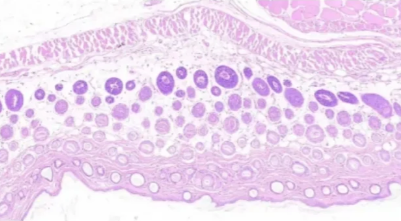

五、切片出现模糊或有杂质

模糊 模糊、杂质伴随气泡